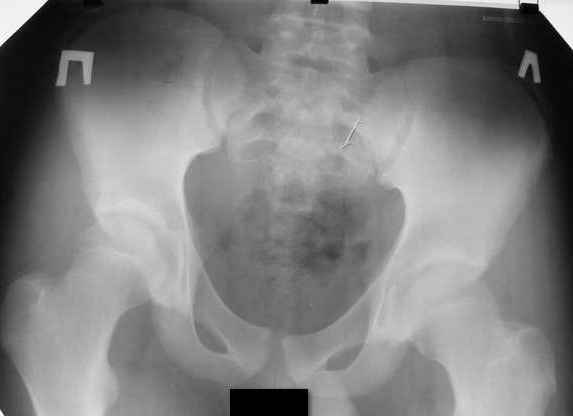

Могу предложить только снимок таза.